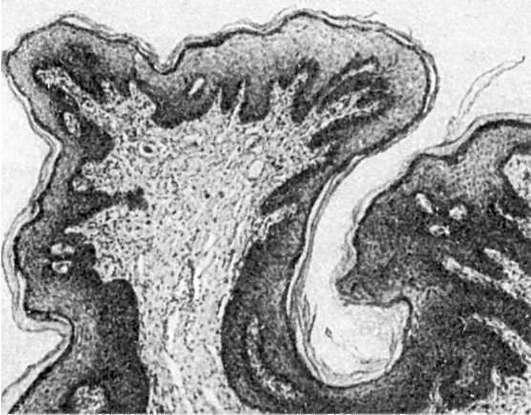

Папиллома (от лат. papilla - сосочек) - опухоль из плоского или переходного эпителия (рис. 100). Она имеет шаровидную форму, плотная или мягкая, с поверхности сосочкового вида (как цветная капуста или ягоды малины), размером от просяного зерна до крупной горошины; располагается над поверхностью кожи или слизистой оболочки на широком или узком основании. Опухоль построена из клеток разрастающегося покровного эпителия, число слоев его увеличено. В папилломе кожи может наблюдаться ороговение разной интенсивности.

Строма выражена хорошо и растет вместе с эпителием. В папилломе сохраняется полярность расположения клеток, комплексность, собственная мембрана. Тканевый

Рис.

100. Папиллома

атипизм представлен неравномерным развитием эпителия и стромы и избыточным образованием мелких кровеносных сосудов.

Папиллома встречается на коже, а также на слизистых оболочках, выстланных переходным или неороговевающим плоским эпителием (слизистая оболочка полости рта, истинные голосовые связки, лоханки почек, мочеточники, мочевой пузырь).

При травме папиллома легко разрушается и воспаляется, в мочевом пузыре может давать кровотечение. После удаления папилломы в редких случаях рецидивируют, иногда (при постоянном раздражении) малигнизируются.